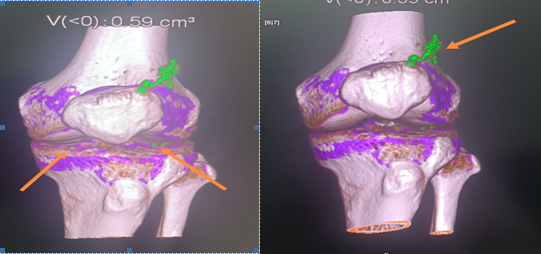

双源CT双能量:和上图为同一个患者,箭头所指为典型尿酸盐沉积,即痛风石。

采用双源CT的双能量成像技术重建出检查区域的三维伪彩图,关节周围可显示紫色和绿色伪彩区域,通过对颜色的识别,能够很直观地观察到痛风结节的存在与否,一般来说,紫色代表钙盐沉积,绿色代表尿酸盐沉积。对于不明原因关节疼痛或不典型部位疼痛患者,双源CT是一种有效的筛查手段。对于已确诊痛风患者,双源CT也可以对痛风石体积进行连续定量检测来评估治疗效果。双能量CT痛风分析具有快速多关节成像,无创,定量,费用低,可重复性高的特点,具有很高的灵敏度,为临床快速诊断起到了至关重要的辅助作用。